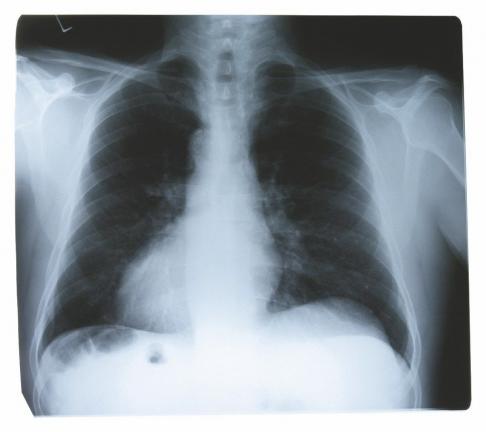

A: Usually, it is a matter of chance. A patient has a chest X-ray because they have pneumonia or as part of a presurgical workup, such as before knee replacement surgery. Then, the radiologist reads the scan and identifies the tumor.